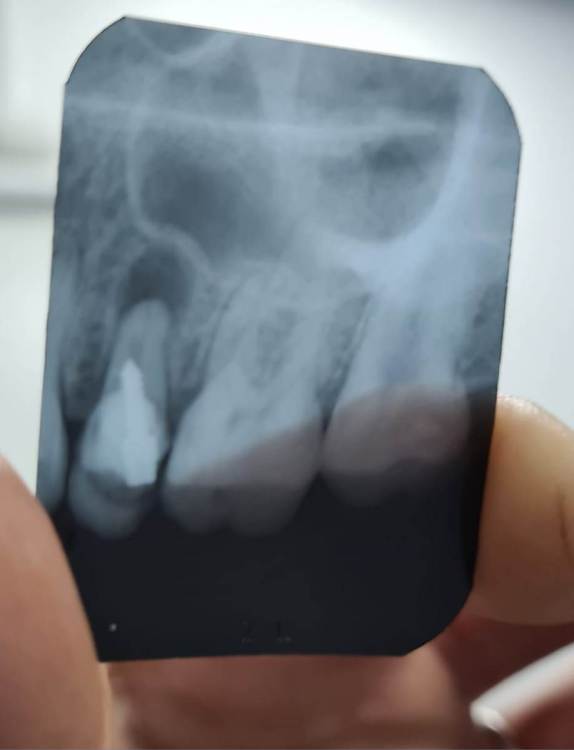

Ольга 777 Опубликовано 23 января, 2023 Поделиться Опубликовано 23 января, 2023 (изменено) Здравствуйте! Есть киста на зубе. Стоит штрифт . Сейчас опухла щека и болит поллица. Удалять зуб жалко. Есть ли шанс сохранить зуб.? Изменено 23 января, 2023 пользователем Ольга 777 Ссылка на комментарий

red_butler Опубликовано 23 января, 2023 Поделиться Опубликовано 23 января, 2023 Здравствуйте. Если судить только по снимку, то удалять. 1 Ссылка на комментарий

Ольга 777 Опубликовано 23 января, 2023 Автор Поделиться Опубликовано 23 января, 2023 (изменено) Я правильно поняла: канал был запломбирован не полностью и штифт давит на стенку канала. Может быть в этом причина возникновения кисты? Изменено 23 января, 2023 пользователем Ольга 777 Ссылка на комментарий

red_butler Опубликовано 23 января, 2023 Поделиться Опубликовано 23 января, 2023 12 минут назад, Ольга 777 сказал: Я правильно поняла: канал был запломбирован не полностью и штифт давит на стенку канала. Может быть в этом причина возникновения кисты? Только по одному снимку ответить не возможно, по снимку зуб сильно разрушен и скорее всего не возможно его восстановить коронкой. 1 Ссылка на комментарий